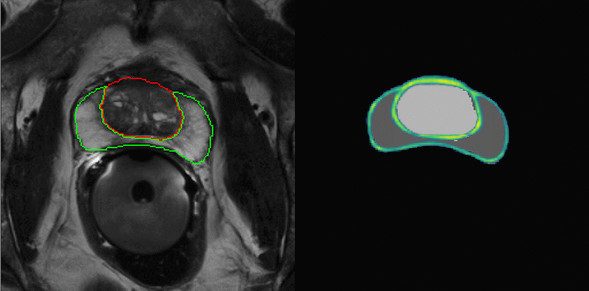

Our research is broad and does not always fit neatly into predefined categories. Nonetheless, a substantial part of our work can be understood as contributing to improved uncertainty quantification and interpretability in machine learning, as well as to the development of methods that generalize across tasks.

Interpretable Machine Learning

Robustness, Safety and Uncertainty

In medical image analysis, confidently predicting something false can have devastating consequences. Apart from achieving high predictive accuracy, one needs to establish…